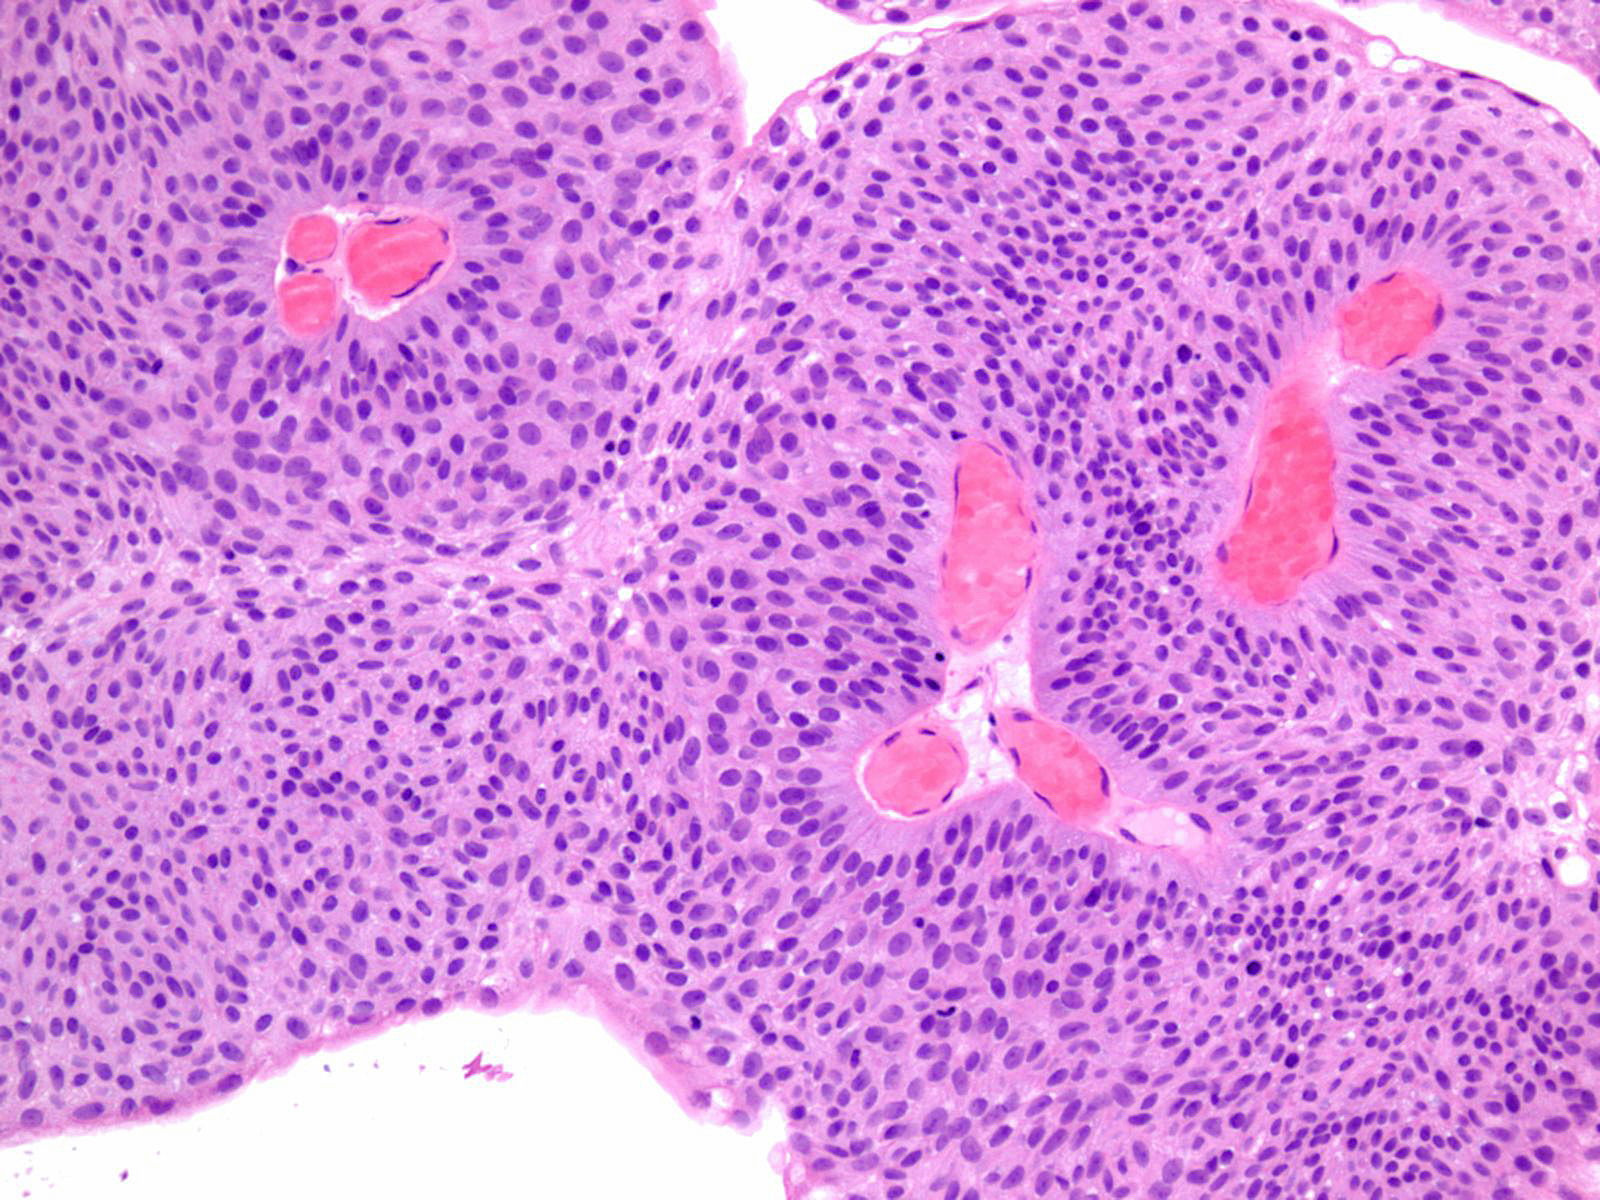

Bladder Papillary Lesions

Case ID: 121